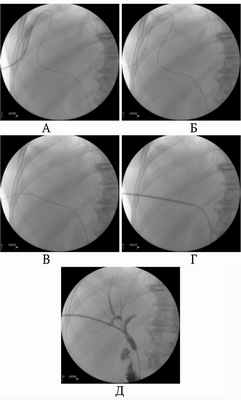

Рис. 2. Восстановление дислоцированного дренажа ЧЧХС по проводнику, оставленному в желчных протоках. А – дренаж в поддиафрагмальном пространстве, проводник остался в просвете желчных протоков. Б – удален дренаж, В – проводник распрямлен, Г – по проводнику в желчные протоки введена игла УДПО, Д – дренаж введен в желчные протоки Учитывая, что большинство осложнений ЧЧХС возникает в результате дислокации дренажа [5], основное внимание уделяли надежной фиксации дренажа в желчных протоках. С этой целью в просвете дренажа и желчных протоков оставляли металлический проводник. Проводник вводили в двенадцатиперстную кишку или сворачивали в протоках, препятствуя его смещению (рис. 1). При этом кончик дренажа не упирался в стенку протока, что исключало «анкерный» механизм дислокации. Кроме того, при развитии неполной дислокации дренажа проводник еще оставался в протоке и по нему можно было вновь ввести выпавший катетер (рис. 2). В результате предпринятых мер профилактики в раннем периоде после ЧЧХС ни у одного больного не было полных дислокаций дренажа и желчеистечения в полость брюшины. Длительность госпитализации после ЧЧХС или ХС в стационарах по месту жительства составила 10.05±1,65 суток. Летальных исходов после успешно выполненного желчеотводящего вмешательства на этом этапе лечения не было. При длительных сроках наружного желчеотведения по холангиостоме у 28 (5,67%) больных произошла дислокация дренажа. Во всех наблюдениях дренаж удалось восстановить по свищевому ходу, оперативных вмешательств не потребовалось. Для восстановления выпавшего дренажа применяли специальные металлические канюли, имеющие оливовидное утолщение на рабочем конце. Катетеризировать желчный пузырь при холецистостомии удалось у всех 55 больных (100%). Технических сложностей и осложнений при чрескожной холецистостомии не отметили. Для холецистостомии использовали дренажи, фиксирующиеся с помощью нити, что у всех больных позволило избежать дислокации. Холецистостомические дренажи всем больным заменяли каждые 3 месяца в плановом порядке. Попытка реканализации желчевыводящих протоков была предпринята у 274 пациентов, что составило 51,6% от общего числа больных с холангиостомами. У 114 пациентов (41,61%) реканализация удалась с первой попытки. У 62 больных (22,63%) потребовалась повторная попытка реканализации. У 98 пациентов (35,77%) преодолеть зону окклюзии желчных протоков не удалось. У 1 больного во время реканализации отметили перфорацию общего желчного протока, которая клинически ничем не проявилась. Других осложнений, связанных с реканализацией желчных протоков, не отметили. Эндопротезирование желчевыводящих протоков выполнили 212 раз у 163 (30,7%) больных. В том числе у 8 человек эндопротезы установили в протоки обеих долей печени. В среднем эндопротезирование выпонияли через 7,6±1,3 суток после успешной реканализации желчных протоков. У 1 (0,6%) пациентки во время эндопротезирования отметили технические сложности, которые привели к неудачной попытке. В отдаленном периоде не было дислокации эндопротезов и окклюзии их за счет прорастания опухолью. У 1 больного (0,6%) после эндопротезирования развились множественные абсцессы печени. Выполнили пункционное лечение, исход благоприятный. У 1 больного эндопротез мигрировал в паренхиму печени. У 108 больных спустя различные сроки возникло нарушение проходимости эндопротеза, потребовавшее его замены. У 24 больных (22,2%) замену выполнили одномоментно. У 83 больных окклюзия эндопротеза привела к развитию холангита. Этим больным эндопротез заменили на наружно-внутренний дренаж, а после купирования холангита у 35 больных (42,2%) повторно установили эндопротез. У 1 больного через 10 месяцев после имплантации выявили закупорку эндопротеза и поддиафрагмальный абсцесс. Выполнили чрескожное дренирование абсцесса и замену эндопротеза на наружно-внутренний дренаж. Выводы. Чрескожное дренирование, реканализация и эндопротезирование желчных протоков, выполненные амбулаторно в условиях дневного стационара по разработанным методикам с помощью специально сконструированных инструментов, сопровождаются малым числом неудач и осложнений. Транспортировка больных перед и после чрескожных желчеотводящих вмешательствах, выполненных амбулаторно по разработанным методикам с помощью специально сконструированных инструментов, не приводит к развитию осложнений. Предложенная организация оказания медицинской помощи является эффективной в лечении больных с механической желтухой. Выполнение чрескожных желчеотводящих вмешательств в условиях дневного стационара улучшает доступность специализированной медицинской помощи данному контингенту больных